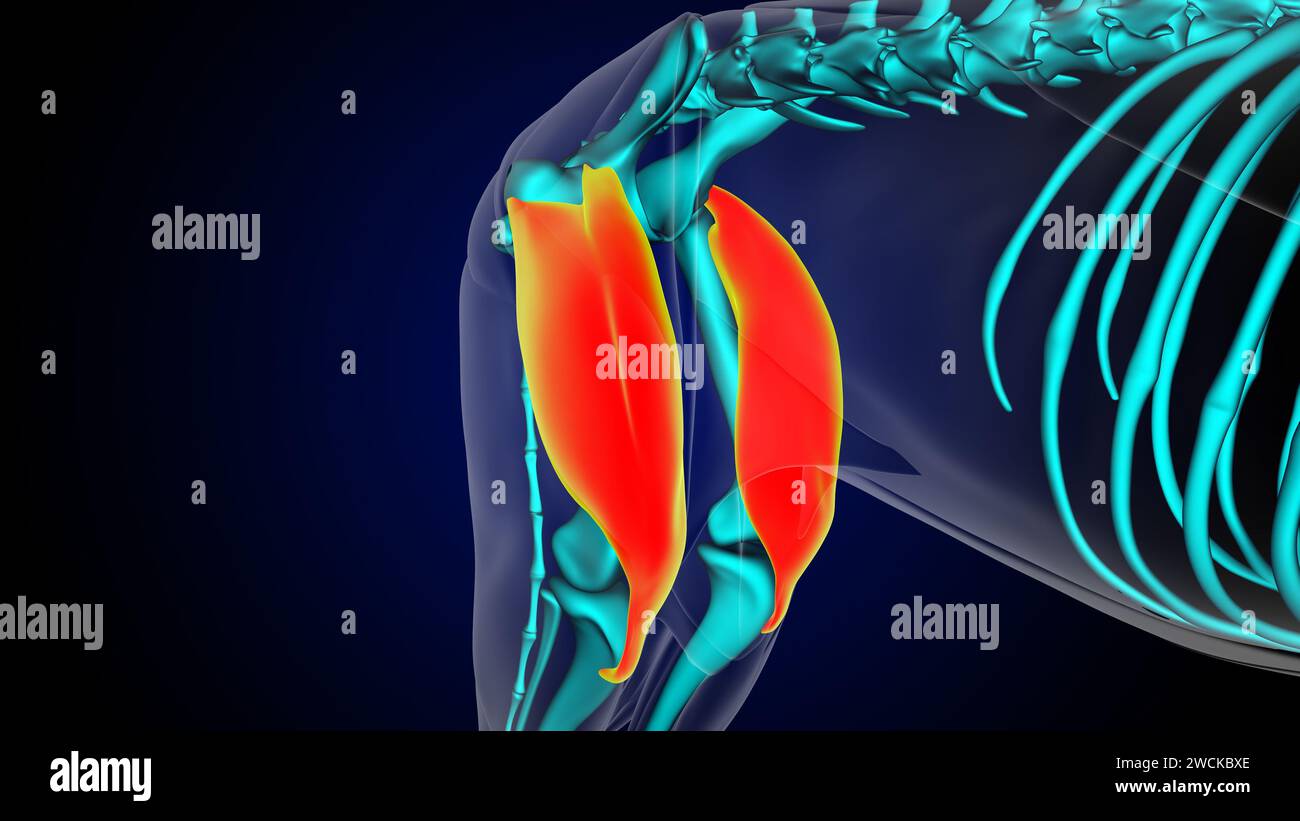

Muscle quadriceps anatomie musculaire du lion pour l'illustration 3D du concept médical Banque D'Imageshttps://www.alamyimages.fr/image-license-details/?v=1https://www.alamyimages.fr/muscle-quadriceps-anatomie-musculaire-du-lion-pour-l-illustration-3d-du-concept-medical-image592954838.html

Muscle quadriceps anatomie musculaire du lion pour l'illustration 3D du concept médical Banque D'Imageshttps://www.alamyimages.fr/image-license-details/?v=1https://www.alamyimages.fr/muscle-quadriceps-anatomie-musculaire-du-lion-pour-l-illustration-3d-du-concept-medical-image592954838.htmlRF2WCKBXE–Muscle quadriceps anatomie musculaire du lion pour l'illustration 3D du concept médical